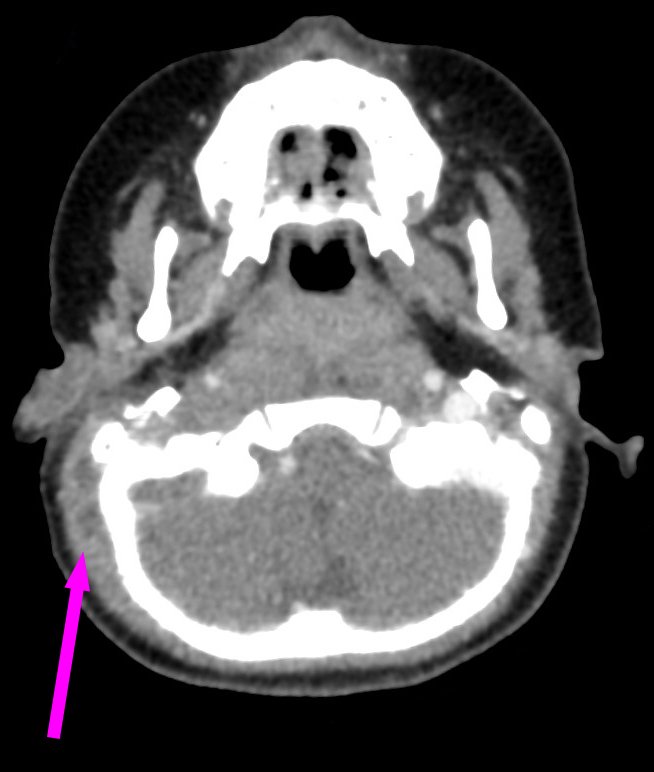

Voici l’imagerie que vous avez demandée. Devant le tableau, le radiologue a également choisi de faire une IRM.

Question 13 : Qu’en pensez-vous ?

Confirmée par la présence d’abcès sous-cutanés rétro-auriculaires droits (cf. question 4)

On voit bien une image plurilobée d’abcès à droite

On peut voir sur le scanner une image très hypodense dans le sinus à droite (alors que le sinus gauche est normalement hyperdense). C’est très visible sur la coupe en IRM avec un caillot hypo-intense au milieu du sinus veineux à droite

Comme expliqué à la question précédente, l’intérêt est de chercher les complications intracrâniennes. Il n’y a pas ici d’abcès intracrânien, mais on retrouve une thrombophlébite importante du sinus sigmoïde droit. Insérer image « Figure10.jpg ». Insérer image « Figure11.jpg ». Insérer image « Figure12.jpg »